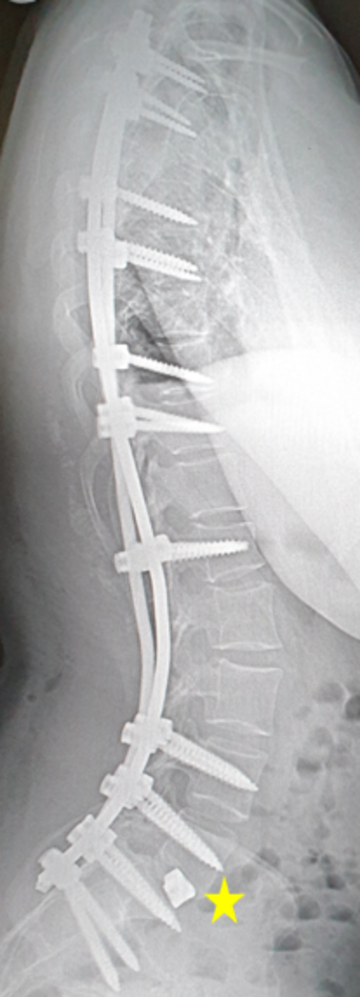

OP-Ergebnis

Harmonisch stehende korrigierte Wirbelsäule mit einer leichten Schultererhöhung, die sich unter Physiotherapie normalisiert hat (Rote Striche). Das Becken steht wieder gerade. Die Rippenstellung hat sich normalisiert.

Überführung der unteren Lendenwirbelkörper in die ursprüngliche Stellung und Ersatz der Bandscheibe mit einem künstlichen Implantat (gelber Stern).